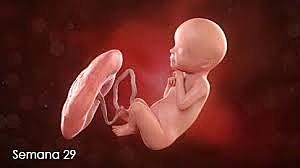

• Semana 29

29

Semana 29

-El cerebro crece rápidamente.

-El sistema nervioso se desarrolla lo suficiente para controlar algunas funciones del cuerpo.

-Los párpados del feto se pueden abrir y cerrar.

-El aparato respiratorio, aunque inmaduro, produce agente tensioactivo (esta sustancia ayuda a que los alvéolos se llenen de aire).